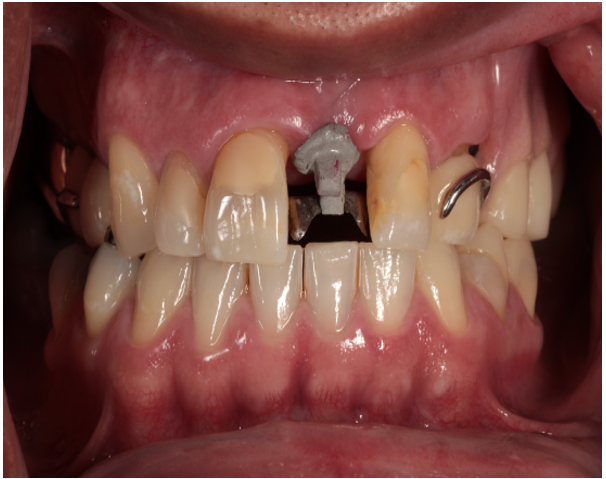

Once the ticonium abutment was welded to the framework, the framework and opposing arch were again scanned. A lithium disilicate crown (e.max, Lithium Disilicate, Ivoclar Vivadent, Liechtenstein) was designed and milled using CAD/CAM technology (Primescan and Primemill, Dentsply Sirona, USA). The crown was crystallized, polished, stained and glazed using MIYO (Jensen, USA). The crown was then cemented to the obturator abutment using a resin cement (Multilink Hybrid Abutment cement, Ivoclar Vivadent, Liechtenstein) (Fig. 4). The obturator was delivered to the patient, and the patient left happy to have the missing tooth replaced without having to endure the process of refabricating the obturator (Figs. 5 and 6).

Figure 4: Crown being placed on obturator abutment to replace missing maxillary central incisor.